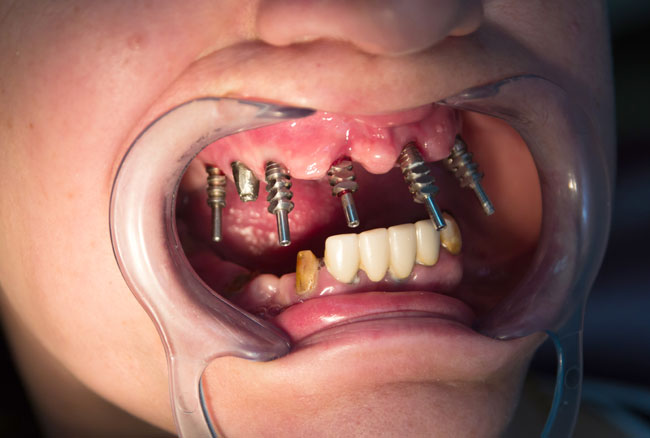

The period of operation of the construction lasted 13 years, after what the bridges that stood on the implants and natural teeth on the maxilla were broken down. In 2013 the plate implant was removed and a fracture of the body of implants 1.3; 1.1, 1.5 and abutments were diagnosed. Available endosseous implant part 1.5 is stable, immobile, with no signs of inflammation of the surrounding bone and mucosa (see Fig. 3)

Taking into account the negative experience of the removable dentures laminar use, there was recommended to install two-stage implants in the upper jaw in area of the missing 1.6; 1.3; 1.2; 2.1; 2.3; 2.5 teeth with the inclusion of a prosthetic construction a cylindrical implant which was set 15 years ago.

In 08.01.2014 the patient were made surgery. In 1.6; 1.3; 1.2; 2.1; 2.3; 2.5 were set Alpha Dent implants 10-13-16 mm length and a diameter of 3.75 – 4.2 mm. Implant 1.2 was installed by passing method between the remaining portions of the previously installed (1999) implants. All implants Alpha Dent were established in “bloodless” way by using tissue punch, without sutures. The postoperative period was uneventful. For rehabilitation period of patient P. made a temporary removable denture in upper jaw was made, which she used for the entire treatment period (from surgery to manufacturing a permanent prosthesis). There was a 5 months period of using a temporary removable prosthesis.

In 02.05.2014 the second stage of rehabilitation was made. Revealed endosseous part 6 Alpha Dent implants in the upper jaw were opened, gums conditioners installed and restored abutment of 15-years old implant in 1.5 using titanium cap. The success rate of implantation in the rehabilitation of patient P. with edentulous maxilla reached 100% (see Fig. 4, 5).